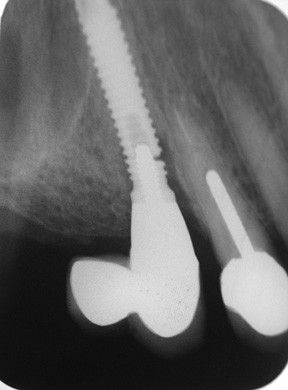

Решающее значение в диагностике периимплантита и его степени принадлежит рентгенологическим исследованиям: прицельной дентальной рентгенографии, ортопантомографии и 3-мерной дентальной компьютерной томографии, с помощью которых выявляется резорбция костной ткани. Вспомогательную роль играют лабораторные исследования – микроскопическое, бактериологическое, морфологическое, ПЦР, биохимическое, рН-метрия ротовой жидкости.

| Периимплантит | 1. Кровоточивость появляется в области периимплантной десны, возникает боль в области имплантата в покое и при жевании. 2. Наблюдается инфильтрат в месте имплантата, в зависимости от стадии периимплантита: в области краевой десны или ближе к переходной складке. 3. В дальнейшем формируется абсцесс и открывается свищевой ход. 4. На ренгенограмме наблюдается характерная кратерообразная деструкция кости в области имплантата. |

Рентгенография. Позволяет отличить периимплантный мукозит от периимплантита: при мукозите на рентгенограмме нет патологических изменений вокруг имплантата; при периимплантите видно убыль кости. Также рентген помогает определить глубину зондирования и увидеть плохое прилегание элементов протеза [14] .

Целесообразно сравнить рентгеновские снимки, сделанные при установке коронки на имплантат и при обращении пациента с мукозитом, чтобы оценить изменения десны и костного края.